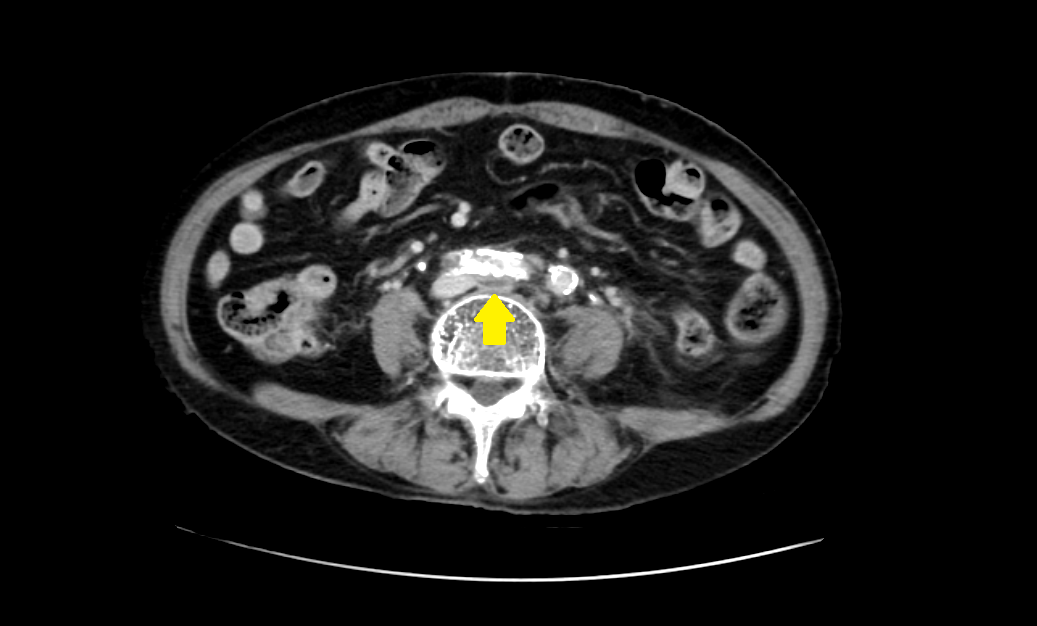

May-Thurner Syndrome(메이-터너 증후군, MTS)은 골반 부위의 해부학적 구조 때문에 생기는 혈관 질환이다. 오른쪽 장골동맥( iliac artery)이 왼쪽 장골정맥(iliac vein)을 누르면서, 왼쪽 다리에서 심장으로 가는 혈류가 방해받는 상태다. 이로 인해 다리에 피가 잘 안 빠지고 붓거나, 심하면 혈전(심부정맥혈전증, DVT)이 생길 수 있다.

- 영상 검사: CT(컴퓨터단층촬영), MRI, 초음파, 혈관조영술 등으로 진단한다.

- 주로 CT 사용: 빠르고 정확하게 혈관 압박 부위를 확인할 수 있다.